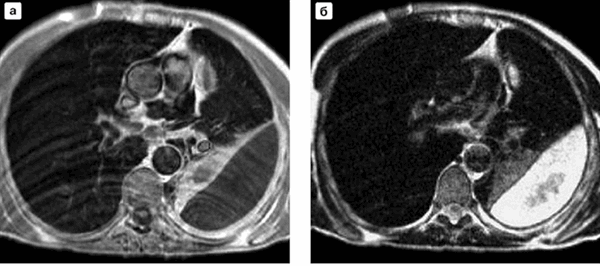

МРТ легких в аксиальной проекции при абсцессе правого легкого (нижняя доля): а - Т1-взвешенное изображение; б - Т2-взвешенное изображение

Эмпиема плевры (скопление гноя) слева на МР-снимках легких в аксиальной проекции: а - Т1-взвешенное изображение; б - Т2-взвешенное изображение